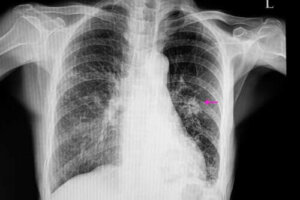

Det första en läkare för närvarande gör är att utesluta att lungknutan är cancerframkallande. Detta beror på att lungcancer är en av de vanligaste cancerformerna. I sådana fall har knölen ett oregelbundet utseende med dåligt definierade kanter; detta syns på röntgenbilder. Dessutom är dessa knölar vanligtvis mindre än de godartade. Elakartade knölar kommer också med vissa riskfaktorer, till exempel:

När detta är gjort måste en läkare utföra vissa avbildningstester för att lokalisera knutan. Dessa bilder gör att läkaren kan observera vissa egenskaper som form och storlek. På så sätt kan läkaren differentiera en godartad knuta från en eventuellt malign.

De vanligaste sätten för diagnostisk är med hjälp av bröströntgen och datortomografier. För att ta reda på den exakta orsaken bakom en lungknuta gör läkare ibland också biopsier, eftersom de på så vis kan analysera vävnaden.